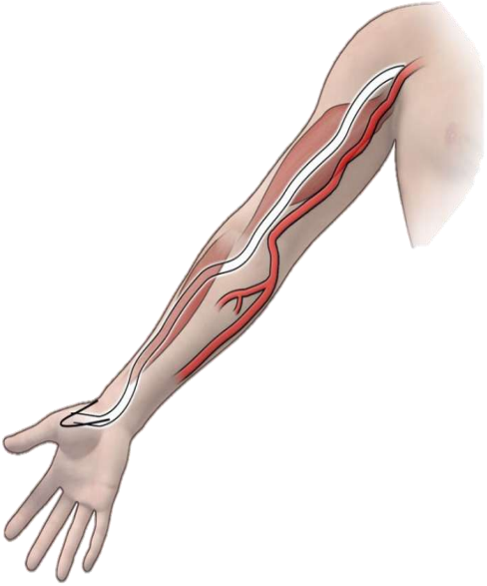

桡动脉位于肱桡腱和桡侧腕屈肌腱之间,从腕部到远端桡骨头有2cm可以触及搏动。初始穿刺部位尽可能在远端,但至少在茎突近端1cm,以避免穿刺屈肌支持带( retinaculum flexorum )和桡动脉小的表浅分支。但任何病人必须有手的双重动脉供血才是经桡动脉路径的适应症。

位置表浅:搏动易于触及和穿刺

管径较细:男,2.7±0.4;女,2.4±0.4

血管壁α1肾上腺素能受体分布多:刺激痉挛

走行变异多,迂曲,分支多:血管损伤及出血基础